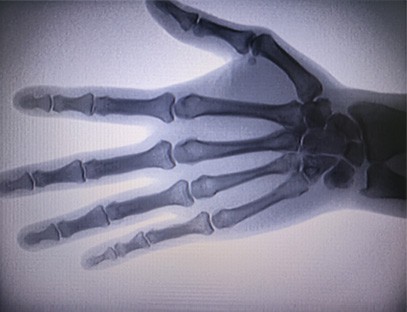

Prijenosni rendgenski aparatje vrlo siguran prijenosni instrument s niskom dozom zračenja koji može dobiti visokokvalitetne slike uz smanjenje izloženosti zračenju. Kompenzira nedostatke velike bolničke opreme i može se pomicati i nositi u bilo koje vrijeme. Posebno prikladno za jedinice i pojedince s nedovoljnim proračunom i malim zahtjevima za slike. Naš rendgenski uređaj nove generacije opremljen je velikim zaslonom visoke razlučivosti od 10 inča, koji ima veći raspon kuta gledanja i može u potpunosti vidjeti kroz cijeli dlan, uključujući prijelome, iščašenja, artritis i tumore kostiju. Može se spojiti na filmski pisač za ispis ortopedskih filmova, a može se koristiti i za industrijsku proizvodnju i testiranje. Nema potrebe za mračnom komorom, izravna perspektiva, promatranje u stvarnom vremenu. Ovaj stroj ima slikovni sustav visoke rezolucije koji može vrlo jasno uhvatiti slike bilo koje koštane strukture. Osigurati najbolju opremu i rješenja za testiranje rendgenskih zraka za proizvođače medicinskih, kućnih ljubimaca, industrijskih i elektroničkih proizvoda, odjele za inspekciju i održavanje te istraživačke laboratorije.

Specijalizacija:Dizajniran za potrebe ortopedskih klinika, posebno pogodan zaRentgensko snimanjeudova kao što su ruke, zglobovi, laktovi, ramena, koljena, gležnjevi itd.

Jasna slika:Napredna digitalna tehnologija snimanja koristi se za dobivanje visokokvalitetnih rendgenskih slika, pomažući liječnicima da točno dijagnosticiraju stanje.